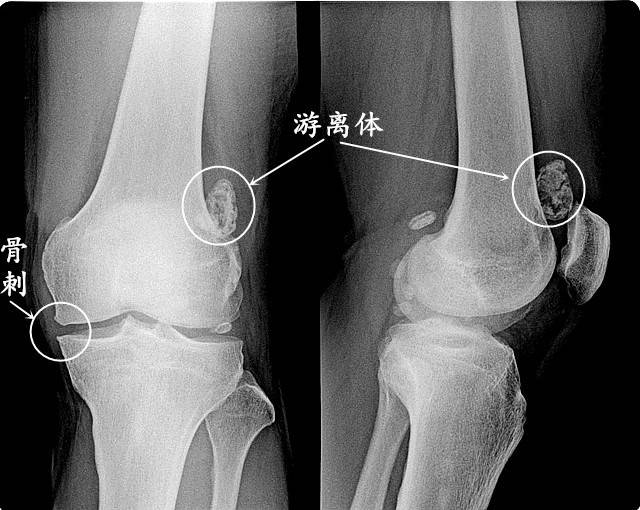

膝关节滑膜炎,在老年人多继发于膝关节骨关节炎,主要是因软骨退变与骨质增生(骨刺)产生的机械性生物化学性刺激,继发膝关节滑膜水肿、渗出和积液等。

关节肿胀、疼痛比较显著,并伴有积液、骨刺、游离骨。